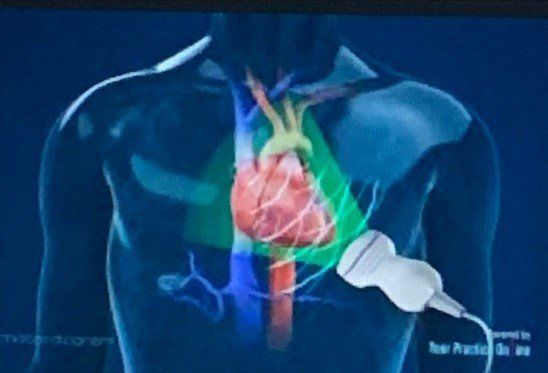

The second type is called a transesophageal echocardiogram (TEE). This is performed when you cannot get clear imaging from the transthoracic echocardiogram due to a heavier body set or other limitations.

The transesophageal echocardiogram is done while laying on your side. A small probe is guided down your throat by the cardiologist along with a technician.

The probe, just like the probe from the TTE, takes images of your heart and its structure from within your body. This test can take around 20-30 minutes.